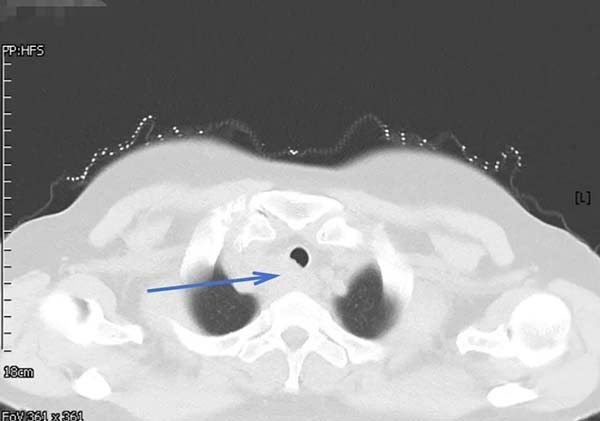

62岁的郑女士近一月来进食时总有食物下咽不畅感,伴有明显哽咽。当地医院胸部增强CT提示食管上段有一约3.7×2.6CM占位性病变,影像报告“不除外食管癌,且可能累及气管后壁”。随后的PET-CT更显示该病灶糖代谢异常增高,代谢活性值高达14.4,强烈指向恶性肿瘤可能。这一系列检查结果让患者及家人陷入焦虑与恐惧。

▲治疗前胸部CT